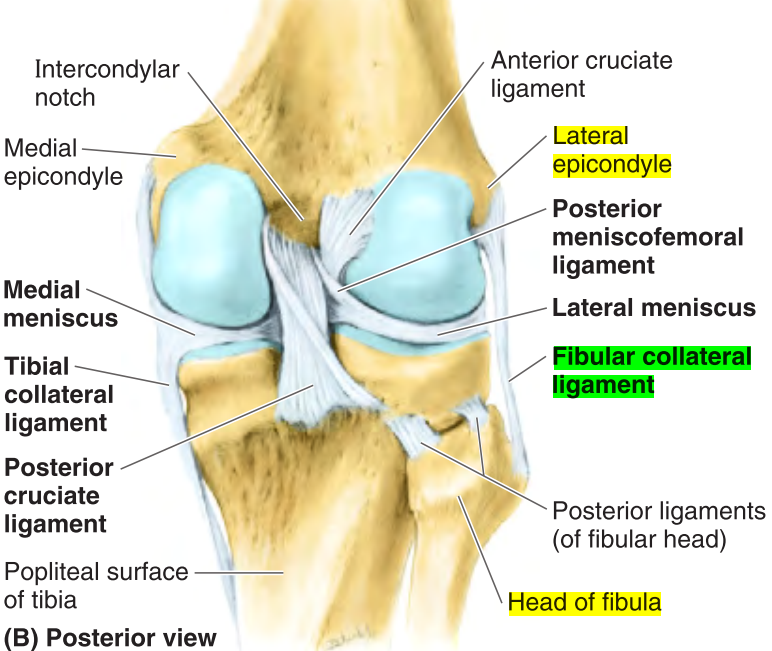

Describe the minisci of the knee joint.

There are two, the lateral and medial menisci. They are incomplete rings of dense connective tissue paritally covering the articular surface of the tibial condyles.

What is the purpose of the lateral collateral ligament?

The lateral (fibular) collateral ligament (LCL) attaches the lateral epicondyle of the femur to the fibular head.